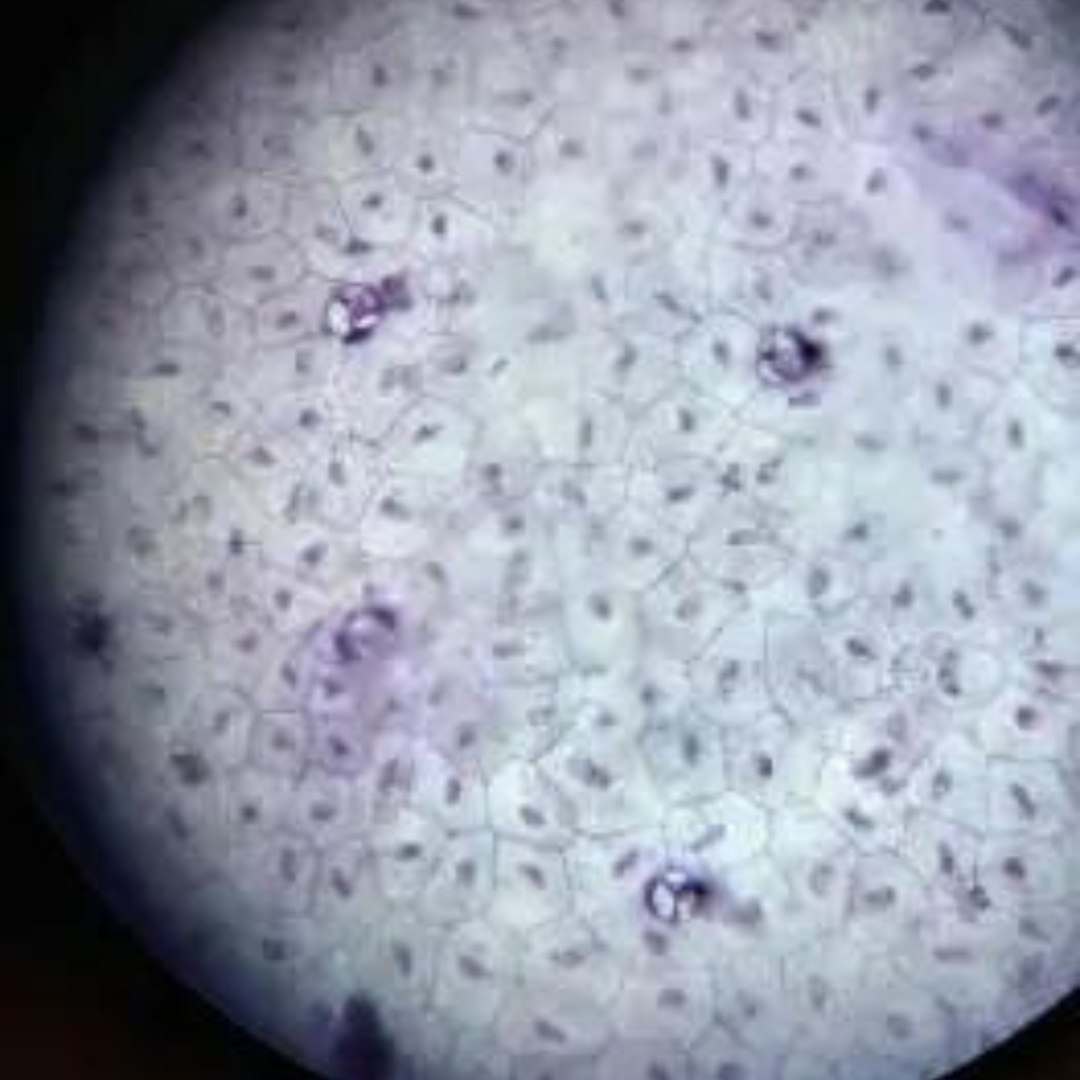

Simple Squamous Epithelium

Simple Squamous Epithelium

Simple Squamous Epithelium

Simple Squamous Epithelium

Simple Squamous Epithelium